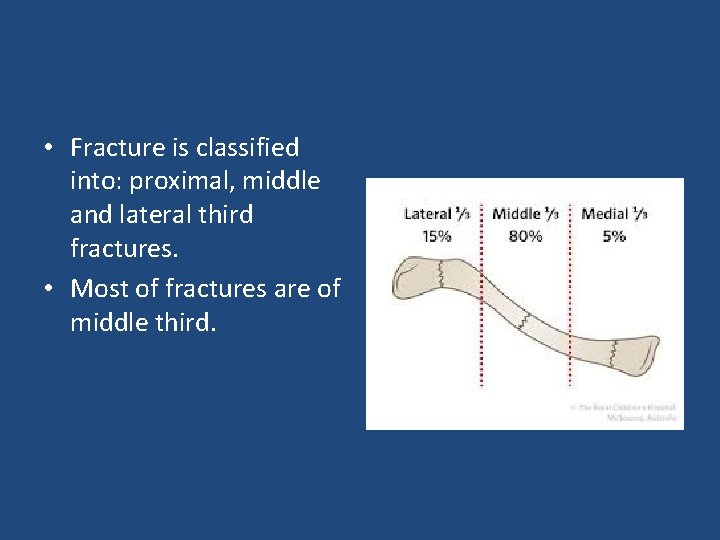

• Fracture is classified into: proximal, middle and lateral third fractures. • Most of fractures are of middle third.